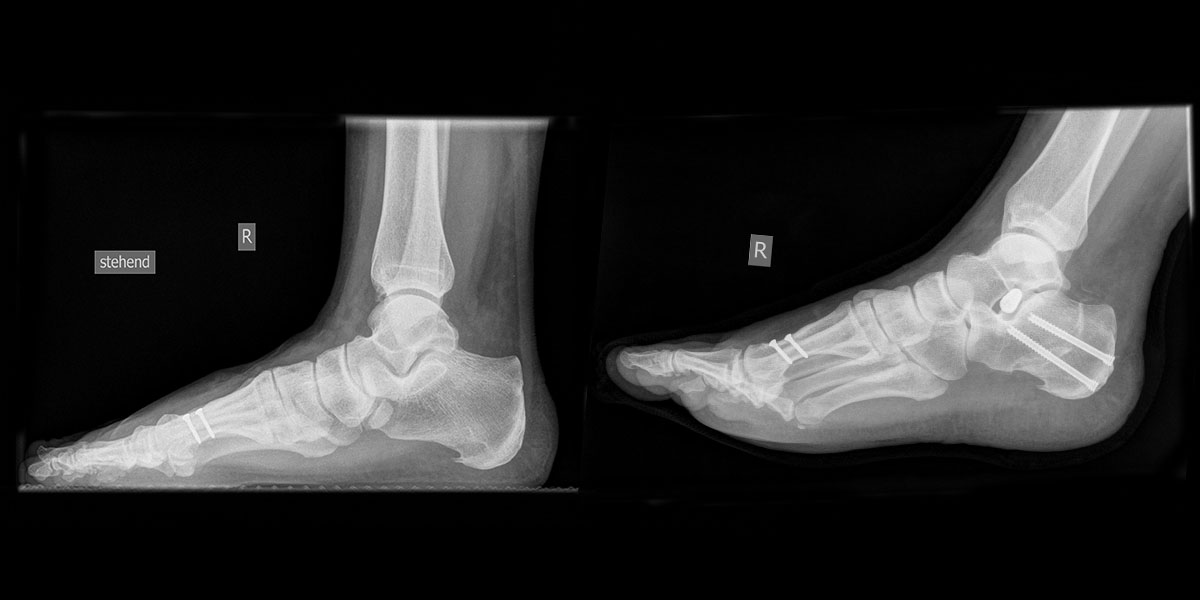

- Röntgenaufnahme des Fußes in 2 Ebenen unter Belastung und die unbelastete Schrägaufnahme (Supinationsaufnahme).

- Röntgen Fuß 2 Ebenen im Stehen und die unbelastete Schrägaufnahme.

- Intra- und postoperativ Röntgenkontrolle Fuß in 2 Ebenen zur Dokumentation. Operational zusätzliche 3 Ebene in 45° Supination.